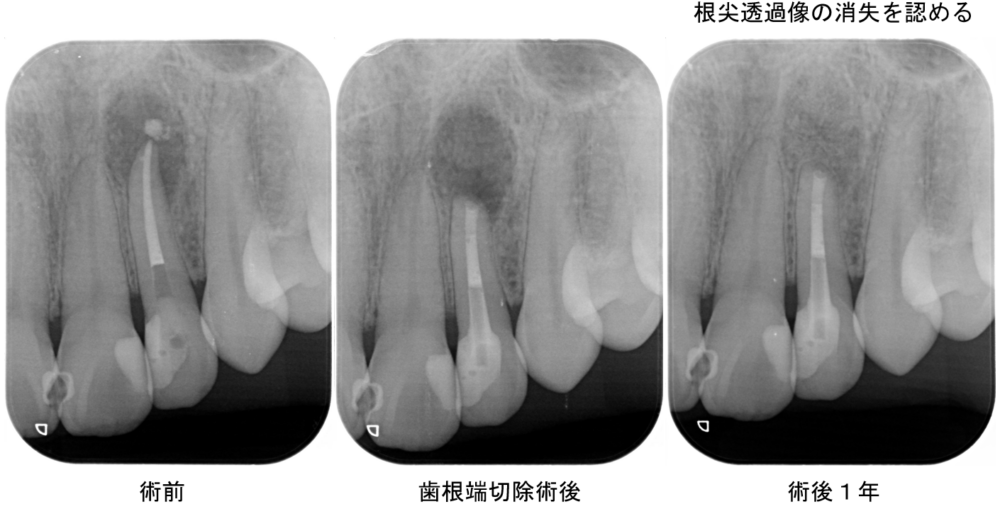

外科的歯内療法(歯根端手術)の症例

症例1

| 患者様データ | 40代 男性 |

| 来院時の主訴 | 「歯茎が腫れてきた。」 |

| 医院の診断 | 慢性根尖性歯周炎 |

| 通院期間 | 1年間 |

| 来院回数 | 6回 |

| 治療費 | 総額:210,000円(税抜) 【内訳】 精密根管治療60,000円+歯根端切除手術60,000円(当院で根管治療を行なっているため差額分のみのご請求)、ファイバーポストコア20,000円、ダイレクトボンディング治療70,000円 |

| リスクと副作用 | ①根管治療歯は長期的には破折するリスク ②長期的なメインテナンスが必要 |

| ここがこだわりのポイント!☝ | MTAを使用した歯根端切除を行うことで、抜歯を回避することができました。 |